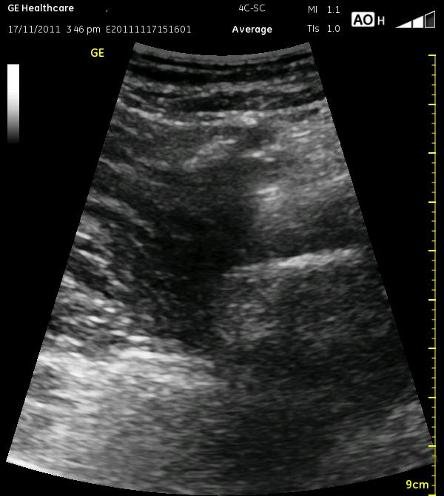

The following ultrasound image shows typical relationships of the sonoanatomy of the anterior sciatic nerve block. The femur is at 4cm on the right (lateral) of the image seen as a bright white horizontal line. Typically, there is a bone shadow below it, though there is some artifact below the femur here. The femoral vessels are seen between the 2cm and 3cm marks just to the right of center as a darkened area. They really can be determined by pausing for the appearance of arterial pulsation and venous compressibility. The adductors are seen to the left of the femur as a darkened area. Just deep to this between the 6cm and 7cm mark is a brightened rectangular shape, the sciatic nerve. The brightness fill fade with rocking of the probe over it. The nerve can be approached from the medial or lateral aspect of the probe, and moving the probe medially will sometimes allow for a better trajectory.

The image above is not an obvious one, and I did that on purpose. You have to get used to the idea that you will not always have a ‘super distinct’ image with this approach, and you will often need to use a number of additional clues to find your target and then to put local around it. I think the only way to really get a handle on being able to identify the basic elements is to look at several images over and over, so I have provided several below for you to use for practice. Note that the sciatic nerve will ‘poke out’ from behind the femur to different degrees depending on your orientation to the femur as well as to how far up or down the femur you go. It will be seen more if you are proximal. See how well you can identify the structures in the images below.